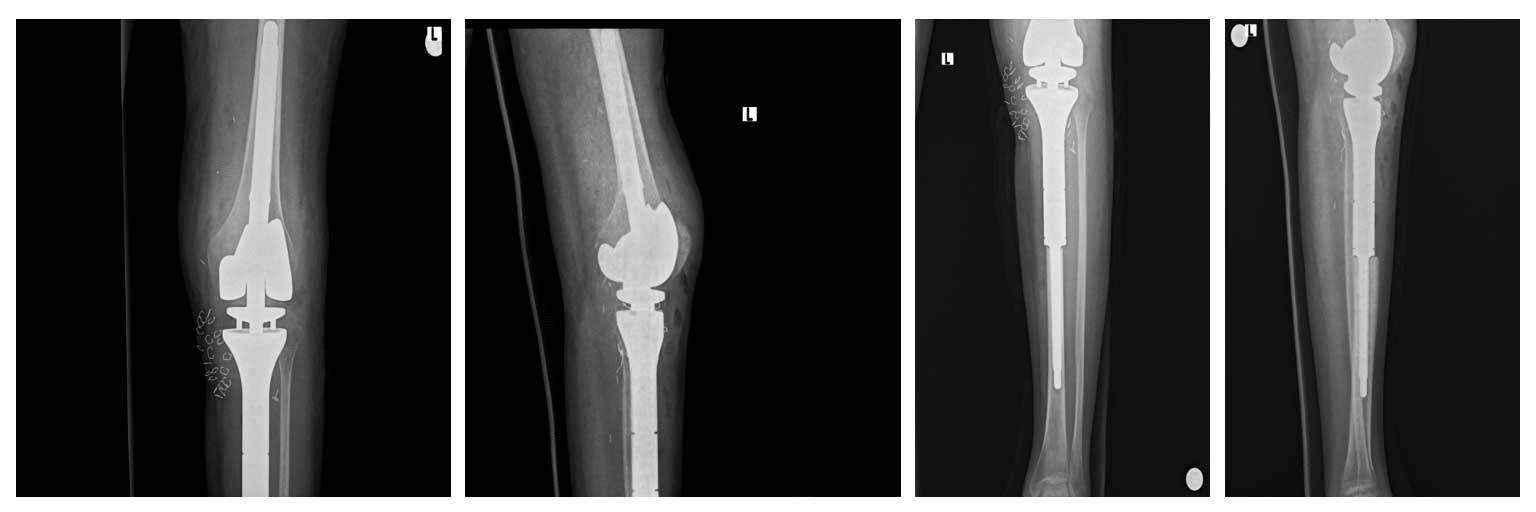

Ameliyat Esnası: Tümör çıkarıldıktan sonra oluşan boşluk, protez uygulanımı, patellar tendonun stüre edilmesi sonrası gastroknemius kas flebi ve cilt grefti uygulanımı görülmekte.

Ameliyat Sonrası: Röntgende rezeksiyon sonrası proksimal tibia tümör protezi ile rekonstrüksiyon görülmekte.